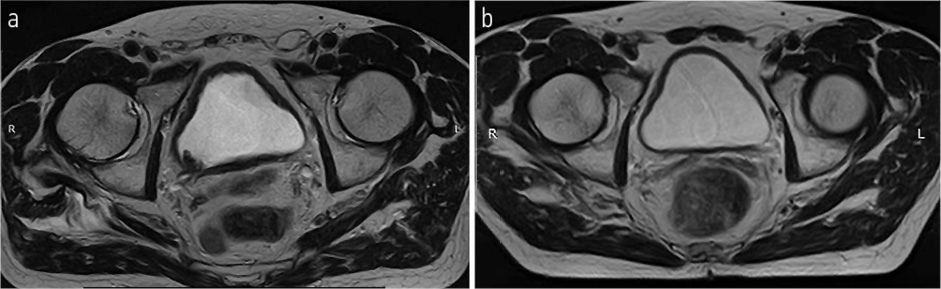

МРТ органов большого таза – ОБП (14.10.2021): По заднеправой стенке мочевого пузыря, в том числе на уровне устья правого мочеточника, визуализируется опухолевое образование неправильной формы с нечеткими неровными контурами со смешанным характером роста. Размер эндофитного компонента 40×21 мм, размер экзофитного компонента – 8×6 мм. Образование вовлекает всю толщу стенки с распространением процесса в паравезикальную клетчатку. Получена МР-картина Cr. мочевого пузыря с выходом процесса за пределы стенки. Удвоение правого мочеточника, уретероэктазия справа. Гиперплазия предстательной железы с наличием участка измененного МР-сигнала в транзиторной зоне левой доли (PI-RADS-4). Метастазы в кости таза. В сравнении с данными исследованиями от 27.08.2021 отмечается отрицательная динамика (рис. 2).

Рис. 2. МРТ ОМТ от 14.10.2021: опухолевое образование неправильной формы с нечеткими неровными контурами со смешанным характером роста. Размер эндофитного компонента – 40×21 мм, размер экзофитного компонента – 8×6 мм.

Fig. 2. Pelvic magnetic resonance imaging (MRI) dated 14.10.2021: tumor mass of irregular shape with ill-defined uneven contours with a mixed growth pattern. The size of the endophytic component is 40×21 mm, and the size of the exophytic component is 8×6 mm.

Рис. 4. МРТ ОМТ от 14.10.2021 в сравнении с МРТ от 27.12.2021. Состояние после 3-го курса лекарственного лечения по схеме EP: опухолевое образование неправильной формы с нечеткими неровными контурами со смешанным характером роста размерами до 14×11 мм с внутрипросветным компонентом.

Fig. 4. Pelvic MRI dated 14.10.2021 in comparison with MRI dated 27.12.2021. State after the 3rd course of drug treatment according to the EP regimen: tumor mass of irregular shape with ill-defined uneven contours with a mixed growth pattern up to 14×11 mm with an intraluminal component.

Рис. 5. МРТ ОМТ от 27.12.2021 в сравнении с МРТ от 24.03.2022. Состояние после 6-го курса лекарственного лечения по схеме EP: отсутствие опухолевого роста.

Fig. 5. Pelvic MRI dated 27.12.2021 in comparison with MRI dated 24.03.2022. State after the 6th course of drug treatment according to the EP regimen: no tumor growth.